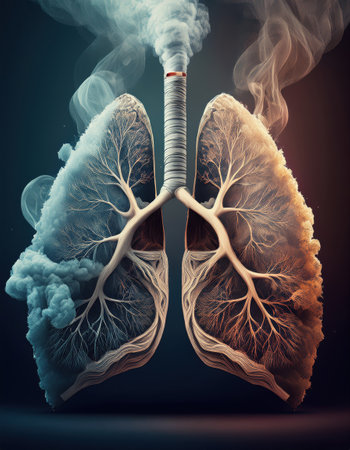

A shot of the lungs and bronchi of a smoker, lungs in smoke. Lung damage from cigarette smoke

?reative magical illustration with Tree branches like the lungs. World No Tobacco Day and Great American Smokeout. Stop smoking and get healthy respiratory organs concept

Smoky Lungs of sick person from which tobacco smoke comes, a diseased destroyed lung, anatomical silhouette. world no tobacco day